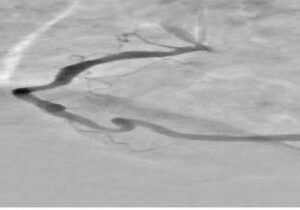

آخوندی با اشاره به دلایل انتخاب این تحقیق، توضیح داد: در آنژیوگرافی قلب، تداخل سایههای ناشی از بافتها و استخوانهای قفسه سینه و همچنین حرکات تنفسی و ضربان قلب باعث میشود تشخیص دقیق عروق کرونری دشوار شود. این مسئله منجر به نیاز به تزریق بیشتر ماده حاجب و دریافت دوز بالاتر اشعه توسط بیمار میشود.

این دانش آموخته دانشگاه صنعتی امیرکبیر با تاکید بر اینکه نتایج این تحقیق موجب بهبود وضوح تصاویر و افزایش دقت در نمایش عروق کرونری قلب شده است، اظهار کرد: این تحقیق به طور ویژه در جهت ارتقای فناوری پردازش تصویر پزشکی و بومیسازی روشهای نوین شبکههای عصبی گامی مؤثر برداشته است؛ چرا که این طرح با کاهش زمان پردازش و افزایش دقت، نسبت به سایر الگوریتمهای سنتی امکان بهرهبرادری بهتر در حوزههای کاربردی را فراهم میسازد.

وی بخش نوآورانه طرح را شامل استفاده از شبکه خودرمزگذار هدایتشده برای بازسازی پسزمینه تصاویر حاوی ماده حاجب از تصاویر بدون ماده حاجب ذکر کرد و افزود: همچنین در طراحی شبکههای عصبی عمیق متناسب بودن با تصاویر آنژیوگرافی بهعلت مقیاس خاکستری آنها و ظرافت عروق در طراحی لحاظ شدهاست.

آخوندی ویژگیهای این طرح را شامل افزایش وضوح عروق کرونری در تصاویر آنژیوگرافی، کاهش نیاز به تزریق مقدار زیاد ماده حاجب و در نتیجه کاهش خطرات مرتبط با آن برای بیمار دانست و افزود: همچنین نسبت به روشهای سنتی، زمان پردازش تصاویر را به طور قابل توجهی کاهش میدهد و میتواند حتی با در اختیار داشتن یک تصویر تکی حاوی ماده حاجب نیز عمل اصلاح و پردازش را انجام دهد. در نهایت، بهرهگیری از فناوری شبکههای عصبی عمیق، امکان استخراج و بازسازی هوشمند پسزمینه و جداسازی بهتر عروق را فراهم میکند و طرح را از نظر علمی و کاربردی در سطح روشهای نوین پردازش تصویر پزشکی قرار میدهد.